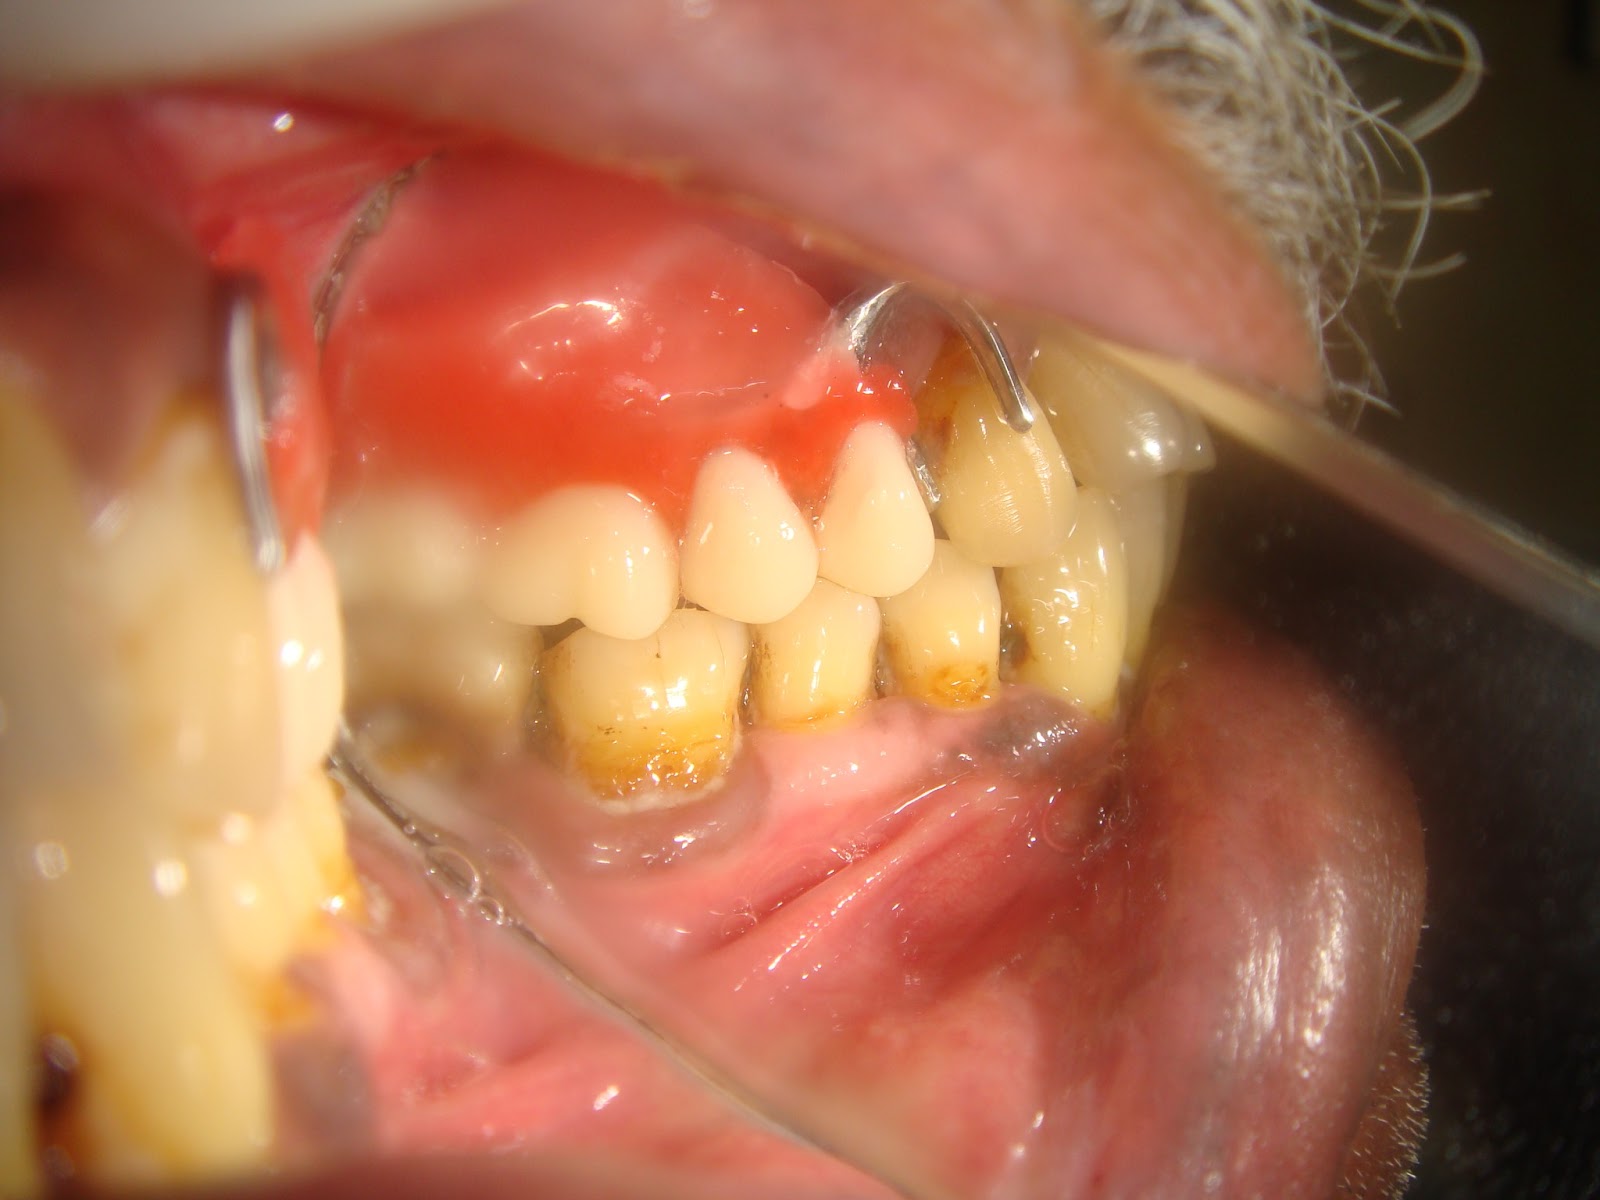

Cast Partial Denture Procedure . Cast metal partial dentures are the most common type of removable partial dentures. A partial denture that can be removed and replaced in the mouth by the patient. The removable partial dentures fabrication consists of six visits. Esthetics, mastication, occlusal support and convenience. You can take the partial denture out yourself, for cleaning and at. Partial dentures are made up of one or more artificial teeth held in place by clasps that fit onto nearby natural teeth. Preliminary impressions, diagnostic casts, and rpd design visit 2 : What is the procedure for having a partial denture? This gives the dentist an opportunity to find out all.

The removable partial dentures fabrication consists of six visits. Cast metal partial dentures are the most common type of removable partial dentures. You can take the partial denture out yourself, for cleaning and at. What is the procedure for having a partial denture? This gives the dentist an opportunity to find out all. Partial dentures are made up of one or more artificial teeth held in place by clasps that fit onto nearby natural teeth. A partial denture that can be removed and replaced in the mouth by the patient. Preliminary impressions, diagnostic casts, and rpd design visit 2 : Esthetics, mastication, occlusal support and convenience.

Cast Partial Denture Procedure Esthetics, mastication, occlusal support and convenience. A partial denture that can be removed and replaced in the mouth by the patient. The removable partial dentures fabrication consists of six visits. Preliminary impressions, diagnostic casts, and rpd design visit 2 : Partial dentures are made up of one or more artificial teeth held in place by clasps that fit onto nearby natural teeth. Esthetics, mastication, occlusal support and convenience. You can take the partial denture out yourself, for cleaning and at. What is the procedure for having a partial denture? This gives the dentist an opportunity to find out all. Cast metal partial dentures are the most common type of removable partial dentures.